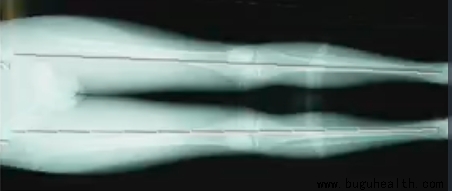

功能性长短腿

皮尺测量法(髂前上棘或肚脐到足踝或足底的长度测试)

皮尺测量的优点是廉价、简便、快捷,但是不如前两者的准确性和可靠性。

NAS

NAS法同样具有廉价、简便、快捷的优点,并且与皮尺测量相比更加准确、可靠,临床上相对用的较多。